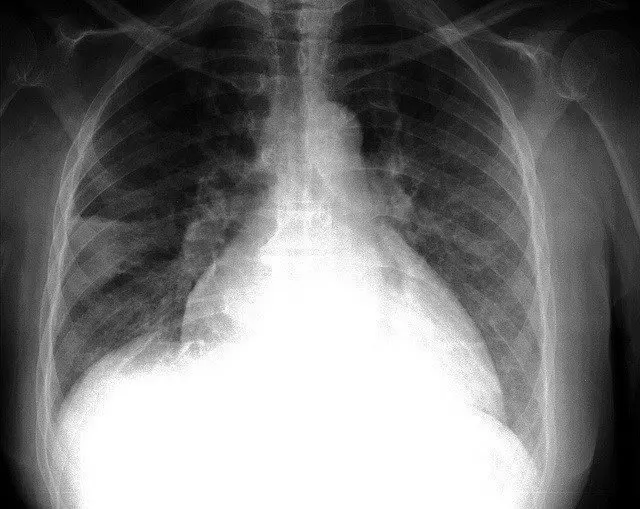

El Servicio de Medicina Intensiva del Hospital Universitario Marqués de Valdecilla ha desarrollado un estudio nacional para detectar precozmente las infecciones en pacientes trasplantados de pulmón mediante nuevos marcadores sanguíneos.

Los resultados de este trabajo, publicados en la prestigiosa revista 'PlosOne', han puesto de manifiesto la utilidad de la procalcitonina (una proteína presente en la sangre) como método para diagnosticar la existencia de un proceso infeccioso en el postoperatorio inmediato del trasplante pulmonar, ha informado el Gobierno de Cantabria en nota de prensa.

Según los expertos, el trasplante pulmonar es la intervención de órgano sólido que cuenta con la esperanza de vida más reducida, debido en parte a las complicaciones que se presentan en los primeros días de postoperatorio del trasplante.

Entre ellas, las más importante son la infección y la disfunción primaria del injerto; dos entidades con formas de presentación muy similares y en ocasiones de difícil diferenciación, pero que cuentan con formas tratamientos diferentes. En el caso de las infecciones, un diagnóstico y tratamiento precoces son fundamentales para lograr una evolución satisfactoria y la resolución del cuadro.